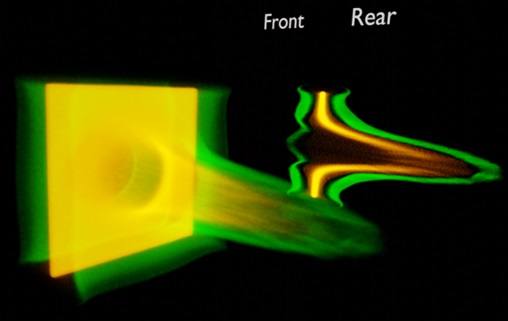

Carbon ion beam to enhance the precision of cancer treatment